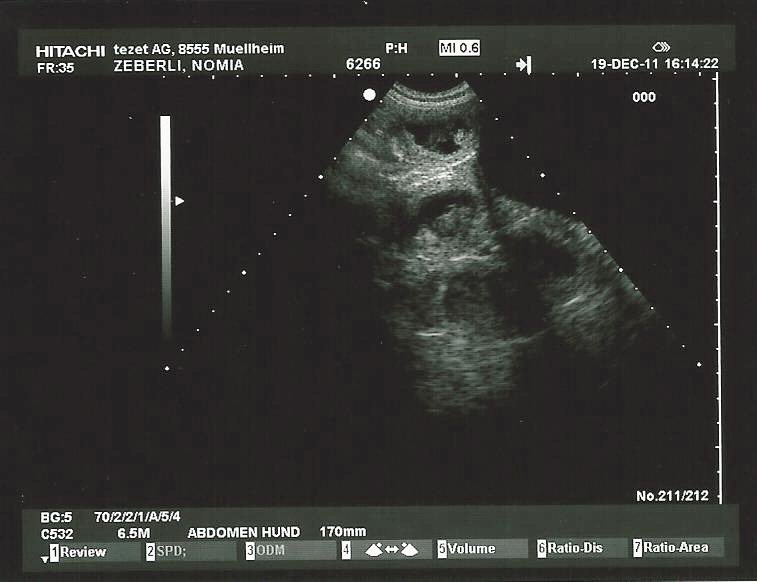

19. Dezember 2012

Freude herrscht!

Nomia ist definitiv trächtig - wir dürfen um den 20 Januar 2012 herum mit Welpen rechnen!